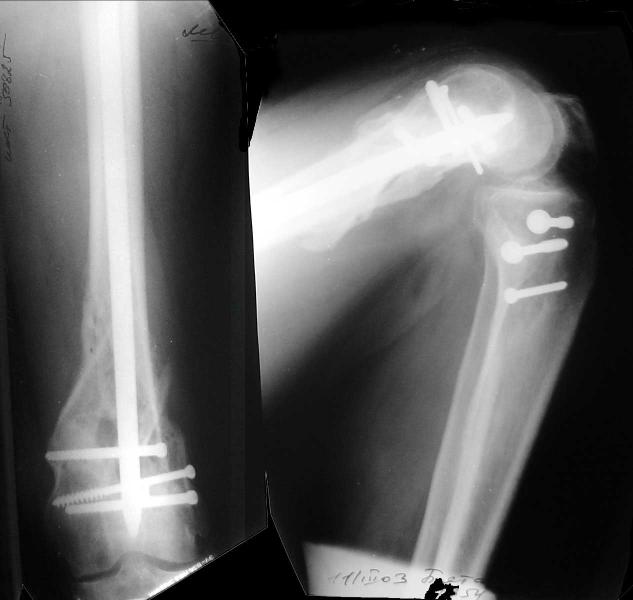

And why LISS is superior here than nail?

Look what we would have done.